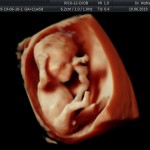

- De la edad gestacional (precisión en el cálculo del tiempo de embarazo).

- Crecimiento fetal.

- Las Estructuras Anatómicas Fetales, diagnóstico precoz de Malformaciones Severas importante mencionar que las malformaciones pequeñas y moderadas solo podrán ser detectadas entre la 18va a 22da semana de gestión (5to mes).